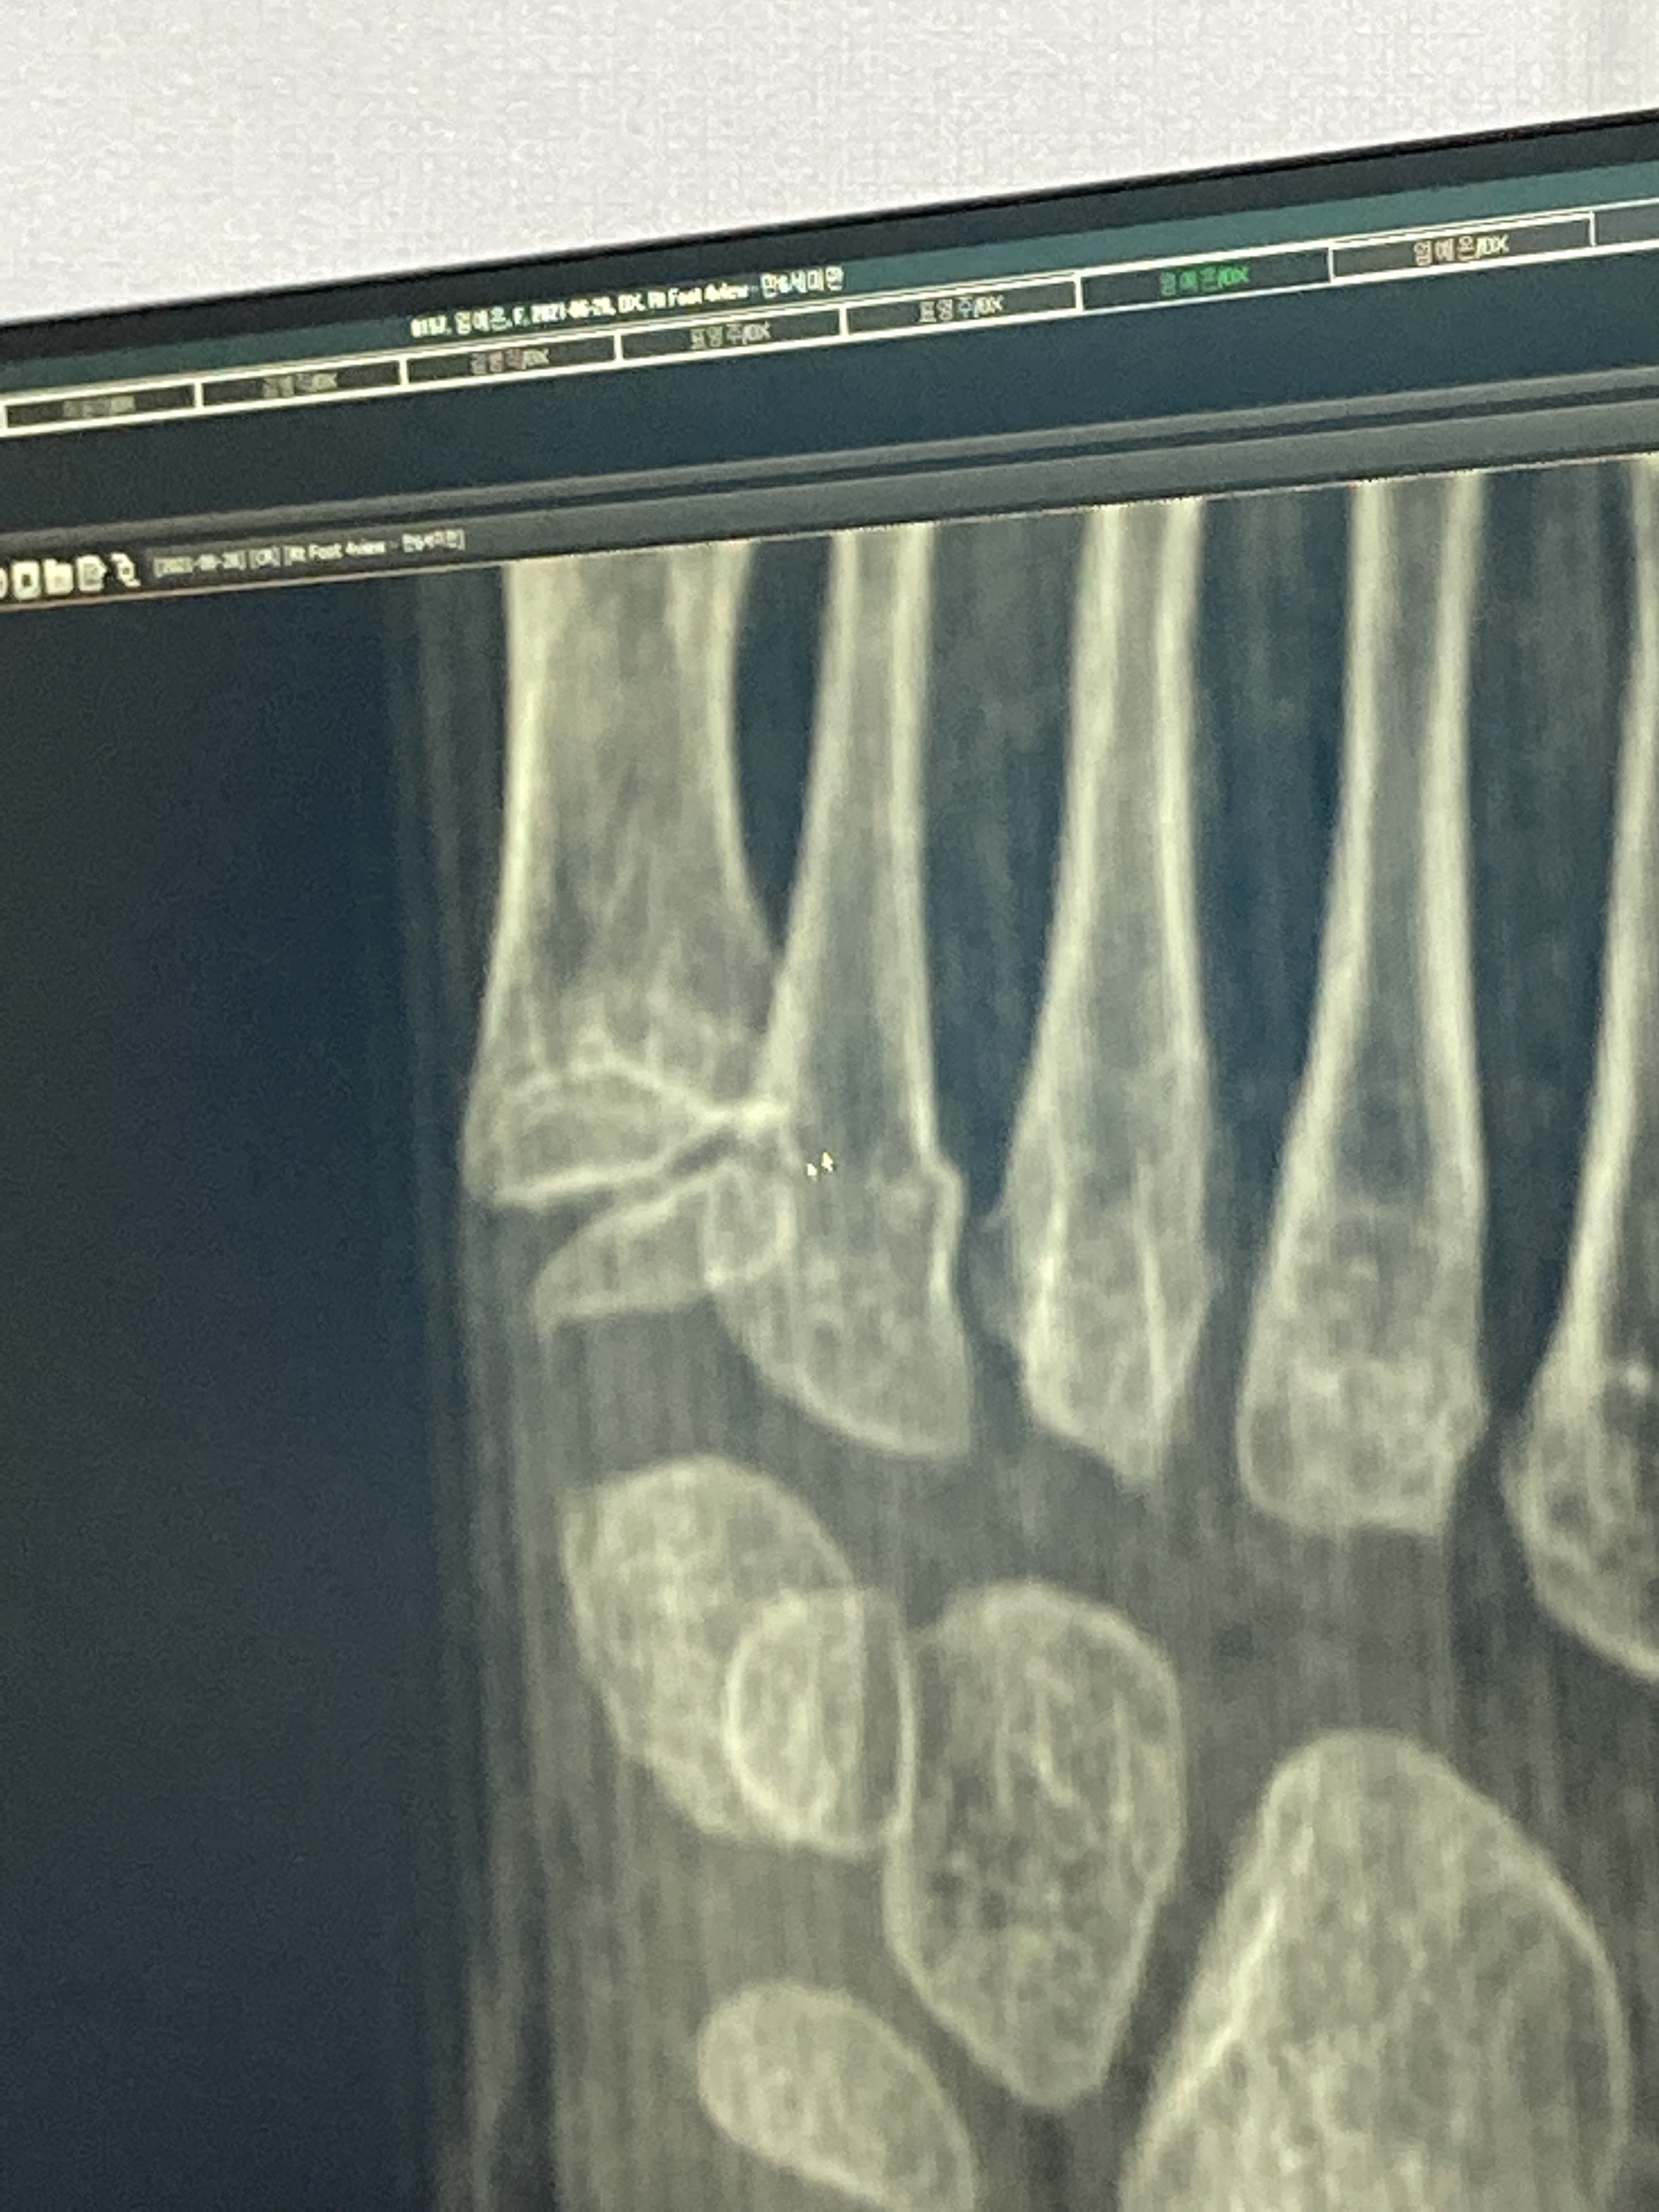

이곳은 좀 더 사진을 디테일하게 꼼꼼하게 찍으시네요~

그리고 원장님이 사진을 세세하게 관찰하시는게 좀 신뢰가 갔습니다.

성장판골절5

골절 의심된다 하십니다. ㅜㅜ

오른발, 왼발 뼈 모양이 다르다고 하시며,,, 성장판 다쳤을 가능성이 크다고,,,

두 분 다 X-ray 만으로도 골절이다 말씀하시네요~

성장판 2형 골절이라고 하십니다.

뼈가 들려있으면 수술해야 하는데, 다행히 들려 있지 않다고 하셨습니다.

어른발과 달라서 아이는 양쪽발을 비교해서 확인하시는데, 일반 정형외과에선 정확히 진단을 못 내리시는 듯 합니다.

그리고 아이들 골절은 첫날, 두째날은 잘 안 보이기도 하고, 며칠뒤에 확인되기도 한다고 들었습니다.